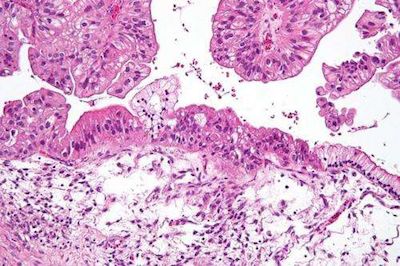

最近,研究者们利用人工智能的手段开发出了快速准确诊断卵巢癌的方法。他们发现血液样本中循环的microRNA网络与卵巢癌的发生之间有很强的相关性。相关结果发表在最近一期的《elife》杂志上。 大部分被诊断患有卵巢癌的女性都处于癌症末期,其中仅有四分之一的患者能够存活5年以上的时间。然而,对于得到早期诊断的女性来说,存活的时间则会显著地增加。目前还没有FDA批准的卵巢癌筛查手段,因此大规模地实现卵巢癌的早期诊断具有很大的挑战。 研究者们分析了血液样本中一类叫做microRNA的分子,这类分子是由基因组非编码区表达产生,能够控制其它基因的表达。 ![]() (图片来源:Nephron /Wikipedia. CC BY-SA 3.0) “microRNA相当于基因组的编辑,当基因表达产生蛋白质的过程中,它们能够发挥调节作用”,该文章的作者,来自BWH的Kevin Elias博士说道。 在实验室阶段,研究者们鉴定了卵巢癌细胞与正常细胞中microRNA的表达水平存在差异,而且与其它分子不同,microRNA能够在血液中循环流动。从而使得其能够在血液样本中检测得到。作者们筛查了135名女性患者的血液样本,从而建立了卵巢癌的microRNA特征库。利用这一信息,能够比较卵巢癌以及正常组织microRNA谱的差异。 之后,作者利用这一模型对另外44名女性进行了检测,验证了其具有较高的准确度。“这一方法的优越性在于误诊的可能性极低,而且会对良性的肿瘤给出阳性的信号,标志这这是一种有效的卵巢癌检查手段”。 |